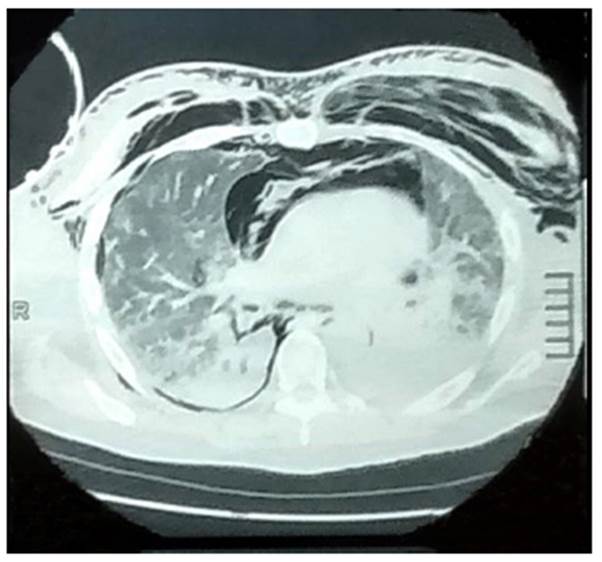

Paciente varón de 49 años, comerciante, natural del distrito de Huacho, provincia de Huaura, ubicada al norte de la ciudad de Lima; tiene antecedentes de obesidad (índice de masa corporal de 41,86) y diabetes mellitus tipo 2, con tratamiento de metformina de 850 mg. El 9 de setiembre de 2020, el paciente ingresa al hospital regional de la misma ciudad llevado por sus familiares, con un tiempo de enfermedad de 10 días, de inicio insidioso y curso progresivo. El cuadro se caracteriza por encefalopatía, tos seca, sensación de alza térmica no cuantificada en el hogar, dificultad respiratoria y cefalea. Examen clínico: presión arterial en 110/70 mmHg, frecuencia respiratoria de 42 por minuto, temperatura de 36 grados centígrados, saturación de oxígeno de 78 % con una fracción inspiratoria de oxígeno del 100 %, con bolsa de reservorio. Piel tibia, húmeda, con tejido celular subcutáneo adecuado y uñas con signos de cianosis periférica. Aparato cardiovascular: ruidos cardiacos rítmicos, bajo tono, no soplos. Aparato respiratorio: murmullo vesicular disminuido en ambos campos pulmonares, crépitos leves en ambas bases pulmonares y roncantes difusos. Abdomen: blando depresivo, ruidos hidroaéreos presentes, no masas palpables. Neurológico: Glasgow 14/15 puntos, reflejo tusígeno positivo, pupilas isocóricas y fotoreactivas. Exámenes de laboratorio: glóbulos blancos: 12 150 x mm3; abastonados: 0 %; hemoglobina: 13,5 g/dl; hematocrito: 40,1 %; plaquetas: 225 000 x mm3; INR: 0,60 S/U; glucosa: 143 mg/dl; creatinina: 0,8 mg/dl; urea: 19 mg/dl; proteínas totales: 6,49 g/dl; albumina: 3,99 g/dl; globulina: 2,50 g/dl; bilirrubina total: 0,54 mg/dl; fosfatasa alcalina:80 UI; aspartato-aminotransferasa: 31 UI; alanina- aminotransferasa:16 UI; prueba rápida para COVID-19 con IgM e IgG positivo; dímero D positivos: 1,45 UGI/L (VN: < 0,5). Análisis de gases arteriales y electrolitos (11/9/20): pH: 7,46; pO₂: 59 mmHg; pCO₂: 40 mmHg, HCO3: 35,6 meq/L; Na: 133 meq/L; K: 3,8 meq/L; Cl: 98 meq/L. (9/9/20): pH: 7,19; pO₂: 69 mmHg; pCO₂: 66 mmHg; HCO₃: 40 meq/L; Na: 140 meq/L; K: 4,1 meq/L; Cl: 104 meq/L. (10/9/20): pH: 7,31; pO₂: 132 mmHg; pCO₂: 84 mmHg; HCO₃: 39,3 meq/L; Na: 140 meq/L; K: 3,7 meq/L; Cl: 98 meq/L. Radiografía de tórax: signos de infiltración alveolar difusa en ambos campos pulmonares (Figura 1).

Figura 1 Infiltrado alveolar bilateral en ambos campos pulmonares